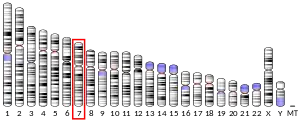

| Aliases | KMT2C, HALR, MLL3, lysine methyltransferase 2C, KLEFS2 | ||||||||||||||||||||||||||||||||||||||||||||||||||

| External IDs | OMIM: 606833 MGI: 2444959 HomoloGene: 46480 GeneCards: KMT2C | ||||||||||||||||||||||||||||||||||||||||||||||||||

- Tan YC, Chow VT (2002). "Novel human HALR (MLL3) gene encodes a protein homologous to ALR and to ALL-1 involved in leukemia, and maps to chromosome 7q36 associated with leukemia and developmental defects". Cancer Detection and Prevention. 25 (5): 454–69. PMID 11718452.

- Ruault M, Brun ME, Ventura M, Roizès G, De Sario A (Feb 2002). "MLL3, a new human member of the TRX/MLL gene family, maps to 7q36, a chromosome region frequently deleted in myeloid leukaemia". Gene. 284 (1–2): 73–81. doi:10.1016/S0378-1119(02)00392-X. PMID 11891048.